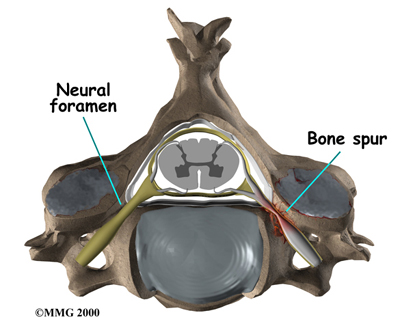

Two spinal nerves exit the sides of each spinal segment, one on the left and one on the right. As the nerves leave the spinal cord, they pass through a small bony tunnel on each side of the vertebra, called a neural foramen. (The term used to describe more than one opening is neural foramina.)

Neural Foramen

As the degeneration continues, bone spurs develop around the facet joints and around the disc. No one knows exactly why these bone spurs develop. Most doctors think that bone spurs are the body's attempt to stop the extra motion between the spinal segment. These bone spurs can cause problems by pressing on the nerves of the spine where they pass through the neural foramina. This pressure around the irritated nerve roots can cause pain, numbness, and weakness in the neck, arms, and hands.

- Degeneration: As the spine ages, several changes occur in the bones and soft tissues. The disc loses its water content and begins to collapse, causing the space between the vertebrae to narrow. The added pressure may irritate and inflame the facet joints, causing them to become enlarged. When this happens, the enlarged joints can press against the nerves going to the arm as they squeeze through the neural foramina. Degeneration can also cause bone spurs to develop. Bone spurs may put pressure on nerves and produce symptoms of cervical radiculopathy.

A foraminotomy is done to open up the neural foramen and relieve pressure on a spinal nerve root. A foraminotomy may be done because of bone spurs or inflammation.